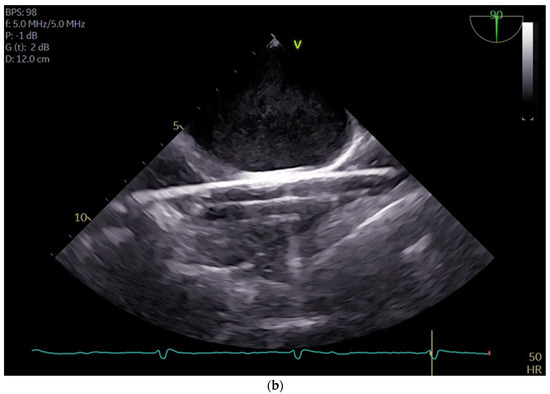

The SVC drainage cannula (Edwards Fr 16/18 OptiSite arterial cannula) is placed via the right jugular vein under ultrasound guidance simultaneously with the central venous catheter insertion. The cannula is positioned caudally to the central venous catheter and other venous lines (see Figure 3a,b). It is important to note that cannulation is performed above the superior thorax aperture to avoid potential complications resulting from intrathoracic vascular damage. We do not perform side-separated cannulation of the central venous catheter and CPB cannula at our center. This approach offers advantages in terms of time management and protection of the contralateral side for possible subsequent punctures during hospitalization. No adverse effects were observed in association with the multiple access procedure.

Figure 3.

(a) shows the catheters inserted in the internal jugular vein right from cranial to caudal as follows: central 4-lumen central venous catheter, 1-lumen 9 FR catheter, and the CPB cannula; (b) shows three guidewires in the right internal jugular vein.